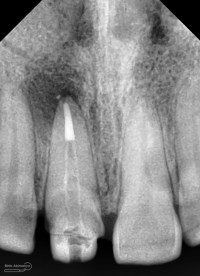

dan saya lebih terkejut ketika melihat foto ronsennya

ini dia ronsen nya….

dari ronsen ini terlihat saluran akar belum diisi dengan baik, kemudian juga ada pasak ulir yang tidak ada retensi sama sekali… di ujung apeks ada gambaran radiolusensi…

Foto radiografis akhir

Terlihat padat dan hermetis dari ujung sampai ke crown….